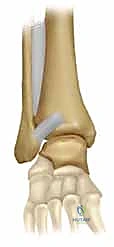

يقوم الدكتور هطيف بعمل شقين جراحيين استراتيجيين:

1. شق على الجانب الخارجي (الوحشي): للوصول إلى عظمة الشظية المكسورة.

2. شق على الجانب الداخلي (الإنسي): للوصول إلى عظمة الظنبوب.

المرحلة الثالثة: رد العظام وتثبيت الكعب الوحشي (الشظية)

يبدأ الجراح عادة بإصلاح الشظية لأنها تعتبر "العمود الفقري" لاستقرار الكاحل. يتم إرجاع قطع العظم إلى مكانها التشريحي الطبيعي (الرد المفتوح). ثم يتم تثبيتها باستخدام شريحة معدنية (Plate) ومجموعة من المسامير (Screws) لتثبيتها بقوة.

المرحلة الرابعة: تثبيت الكعب الإنسي (الظنبوب)

بعد استقرار الجانب الخارجي، ينتقل الجراح للجانب الداخلي. يتم تنظيف منطقة الكسر من أي أنسجة محشورة، ثم يتم رد الكعب الإنسي وتثبيته غالباً باستخدام مسمارين طويلين (Cancellous screws) أو تقنية الأسلاك والشد (Tension band wiring) حسب شكل الكسر.